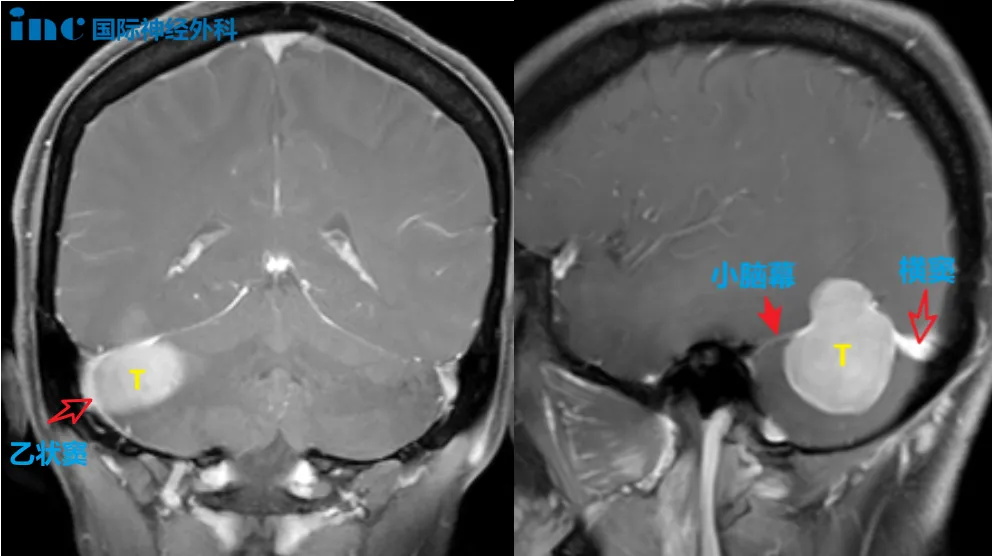

較大天幕腦膜瘤

病灶與腦膜呈寬基底且向幕上凸起,邊界清晰,右側(cè)小腦半球受壓。

▼腫瘤位置與乙狀竇、橫竇關(guān)系密切

腫瘤位置與乙狀竇、橫竇關(guān)系密切

由于其體大與周?chē)M織包括神經(jīng)、血管或者四腦室底黏連重,且后顱窩空間狹小,而腫瘤質(zhì)地又較硬韌,手術(shù)持續(xù)時(shí)間較長(zhǎng),這些都會(huì)對(duì)術(shù)者的圍手術(shù)期處理策略、手術(shù)技術(shù)、以及體力(耐力和毅力)是一個(gè)挑戰(zhàn)。